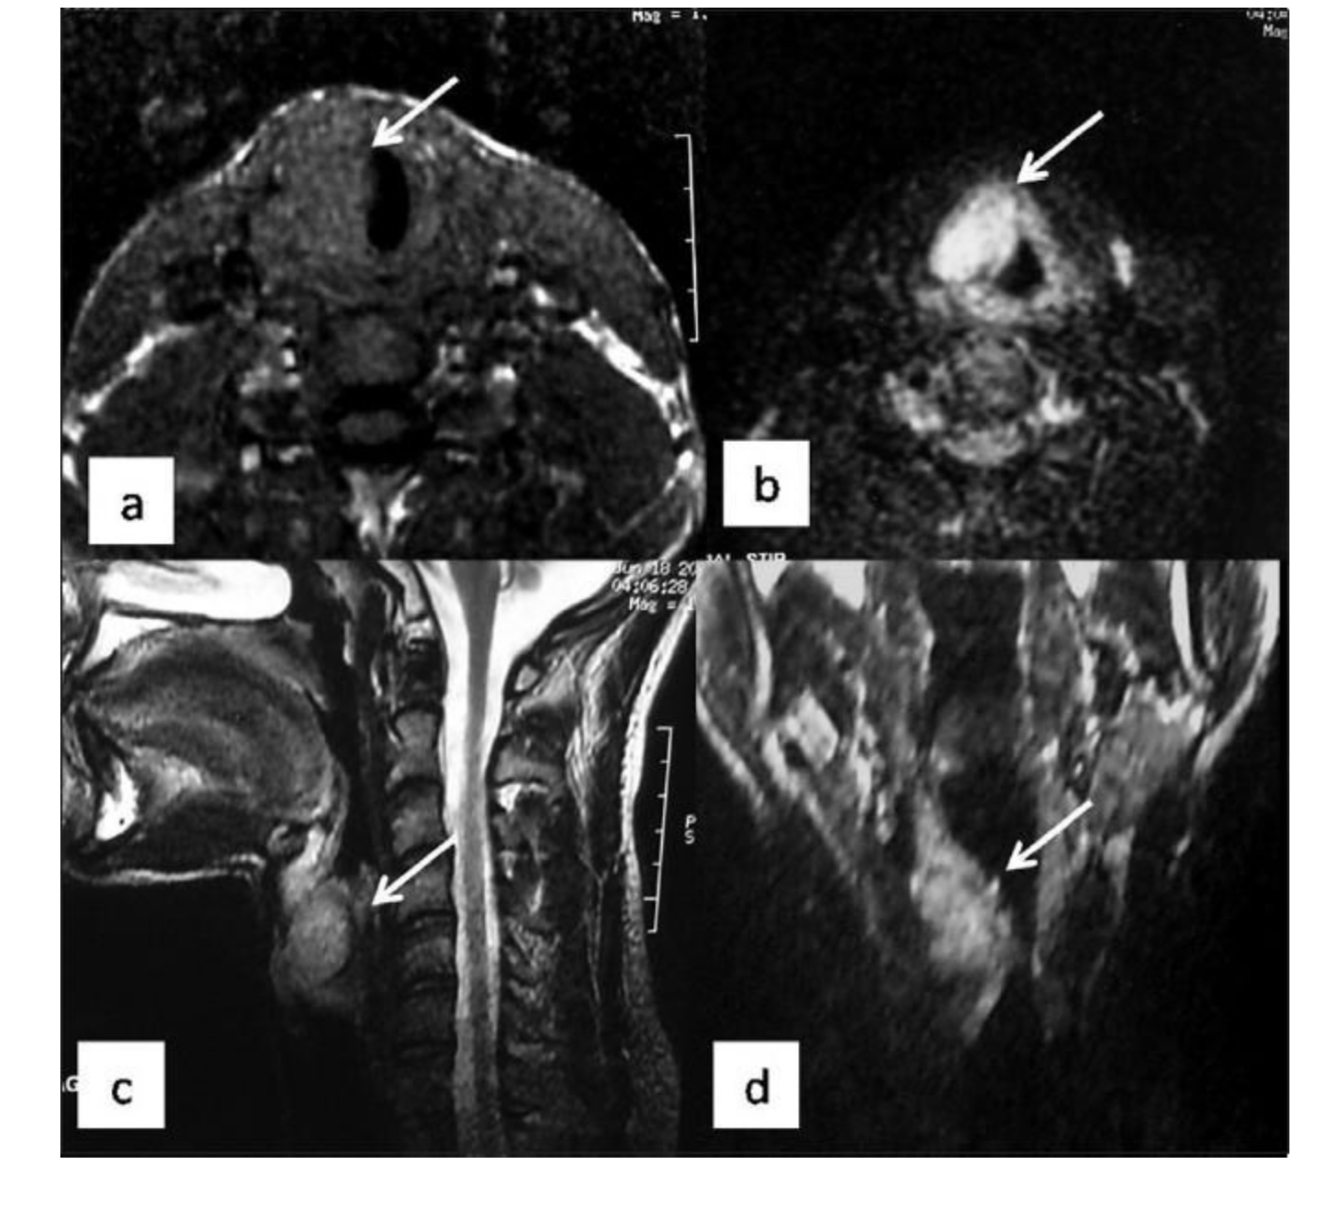

What pathology indicated?

A

Mass - right parotid gland

What does arrow indicate?

left parotid mass

Q

What does arrow indicate ?

submandibular gland

Vocal cord Schwannoma